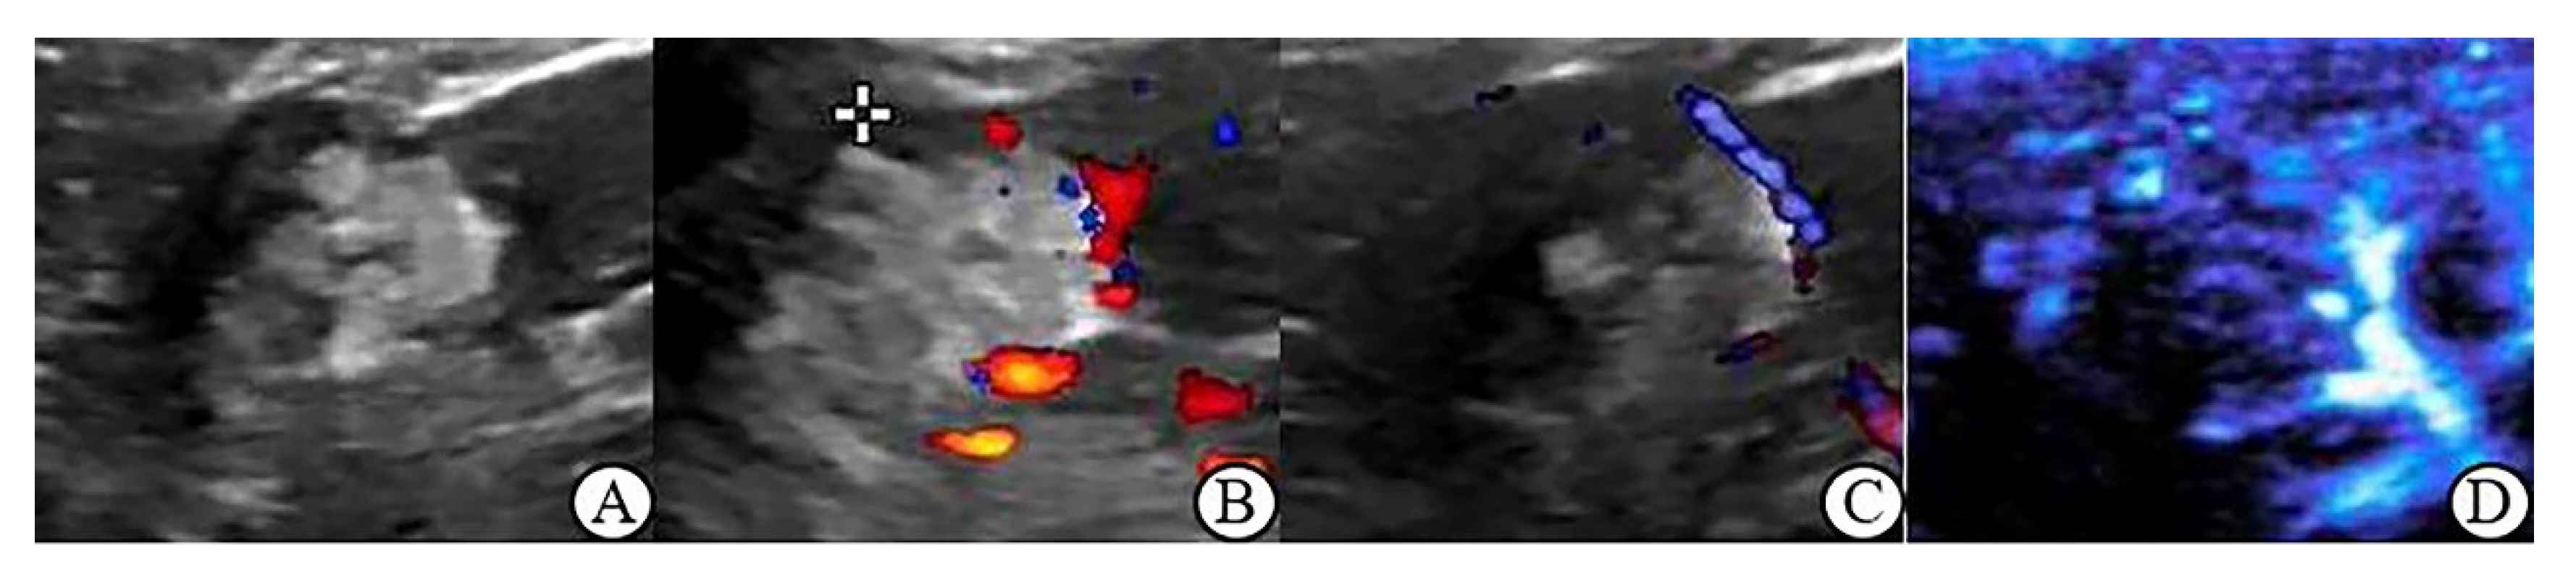

3.4. CDFI, PDI and MFI Evaluation of Blood Flow Characteristics in Benign and Malignant Renal Tumors > 4 cm

3.5. Peripheral Blood Flow Characteristics of Renal Tumor in MFI Mode